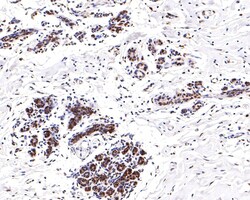

Invitrogen™ Phospho-ATF2 (Thr71) Recombinant Rabbit Monoclonal Antibody (SC05-90)

The transcription factor ATF-2 (also called CRE-BP1) binds to both AP-1 and CRE DNA response elements and is a member of the ATF/CREB family of leucine zipper proteins. ATF-2 interacts with a variety of viral oncoproteins and cellular tumor suppressors and is a target of the SAPK/JNK and p38 MAP kinase signaling pathways. Various forms of cellular stress, including genotoxic agents, inflammatory cytokines and UV irradiation, stimulate the transcriptional activity of ATF-2. Cellular stress activates ATF-2 by phosphorylation of Thr69 and Thr71. Both SAPK and p38 MAPK have been shown to phosphorylate ATF-2 at these sites in vitro and in cells transfected with ATF-2.

| Immunohistochemistry (Paraffin), Western Blot, Immunocytochemistry | |